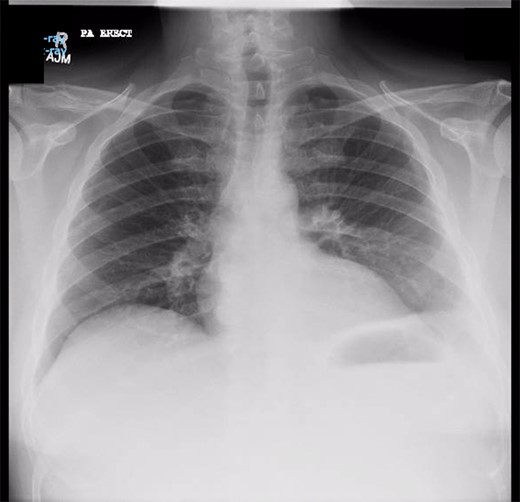

Chest X-ray in ICU following drainage showed what was thought to be Pneumomediastinum (Figs 1 and 2), and given this concern he was referred to the Cardiothoracic service. Subsequent CT suggested a large loculated hydro-pneumothorax, which in retrospect represented the drained Pseudocyst communicating through the diaphragm (Figs 3 and 4).

Area of communication between the drained Pseudocyst and the Left Pleura. Space noted with arrow.